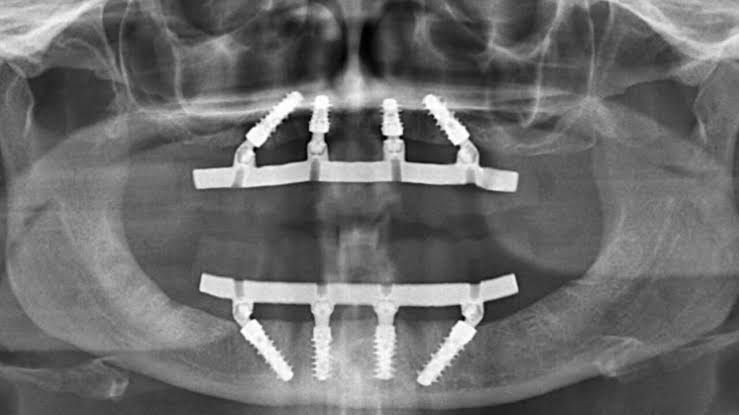

Indicada para quem perdeu todos os dentes da arcada. São 12 dentes fixos sustentados em 4 a 6 implantes, garantindo estabilidade total.

Prótese fixa sustentada por apenas 4 implantes, ideal para quem tem pouca estrutura óssea para evitar enxerto ósseo.